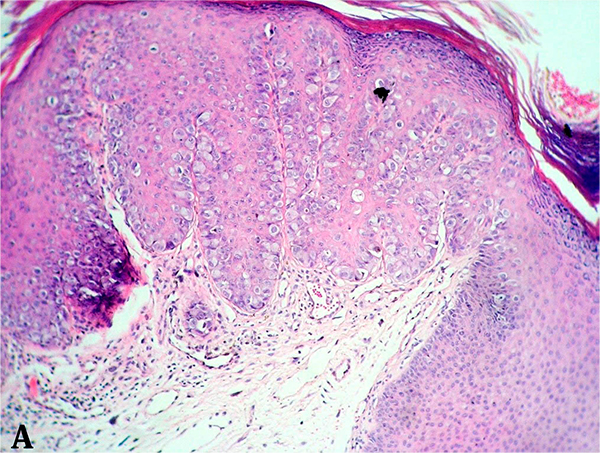

Haga usted el diagnóstico. Parte 1

Haga usted el diagnóstico. Parte 2